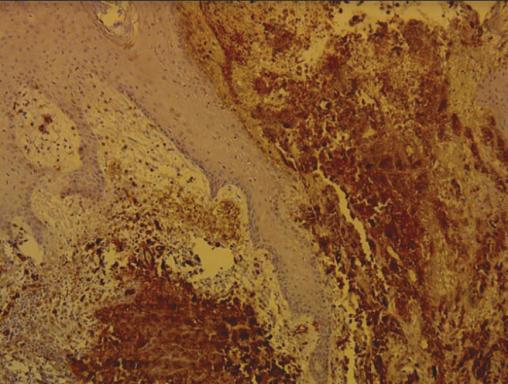

Cette femme de 34 ans consultait pour l’apparition récente (1 mois) de lésions bourgeonnantes violacées saignant au contact sur la face antérieure de la jambe droite ; ce membre étant le siège d’un lymphœdème chronique idiopathique depuis 4 ans. L’examen notait des lésions nodulaires angiomateuses, dont la plus grande avait un grand axe de 3,5 cm, ulcérées au centre, saignant au contact (fig. 1 ). La biopsie cutanée montrait un aspect morphologique et immunohistochimique en faveur d’un angiosarcome (fig. 2 ). La tomographie par émission de positons (fig. 3 ) montrait des plages hypermétaboliques multiples osseuses et tissulaires ainsi que de volumineuses adénopathies multiétagées. Le diagnostic retenu était celui d’angiosarcome métastatique. La patiente décédait une semaine plus tard.

Le syndrome de Stewart-Treves est une entité rare correspondant à un angiosarcome cutané compliquant un lymphœdème chronique. Son incidence serait de 0,07 à 0,45 % chez les patients ayant survécu au moins 5 ans après une mastectomie, avec un délai de 5 à 11 ans. Le pic d’âge se situe entre 65 et 70 ans.1 La survenue sur lymphœdème chronique idiopathique du membre inférieur chez une femme jeune avec un délai de 4 ans est exceptionnelle. La physiopathologie est encore mal élucidée. Le diagnostic histologique est difficile en raison de la double composante vasculaire et lymphatique. L’imagerie, en particulier le TEP-scan, est utile en période préopératoire, à la recherche de localisations secondaires. La chimiothérapie néoadjuvante associée à une chirurgie radicale suivie d’une radiothérapie sont recommandées.2